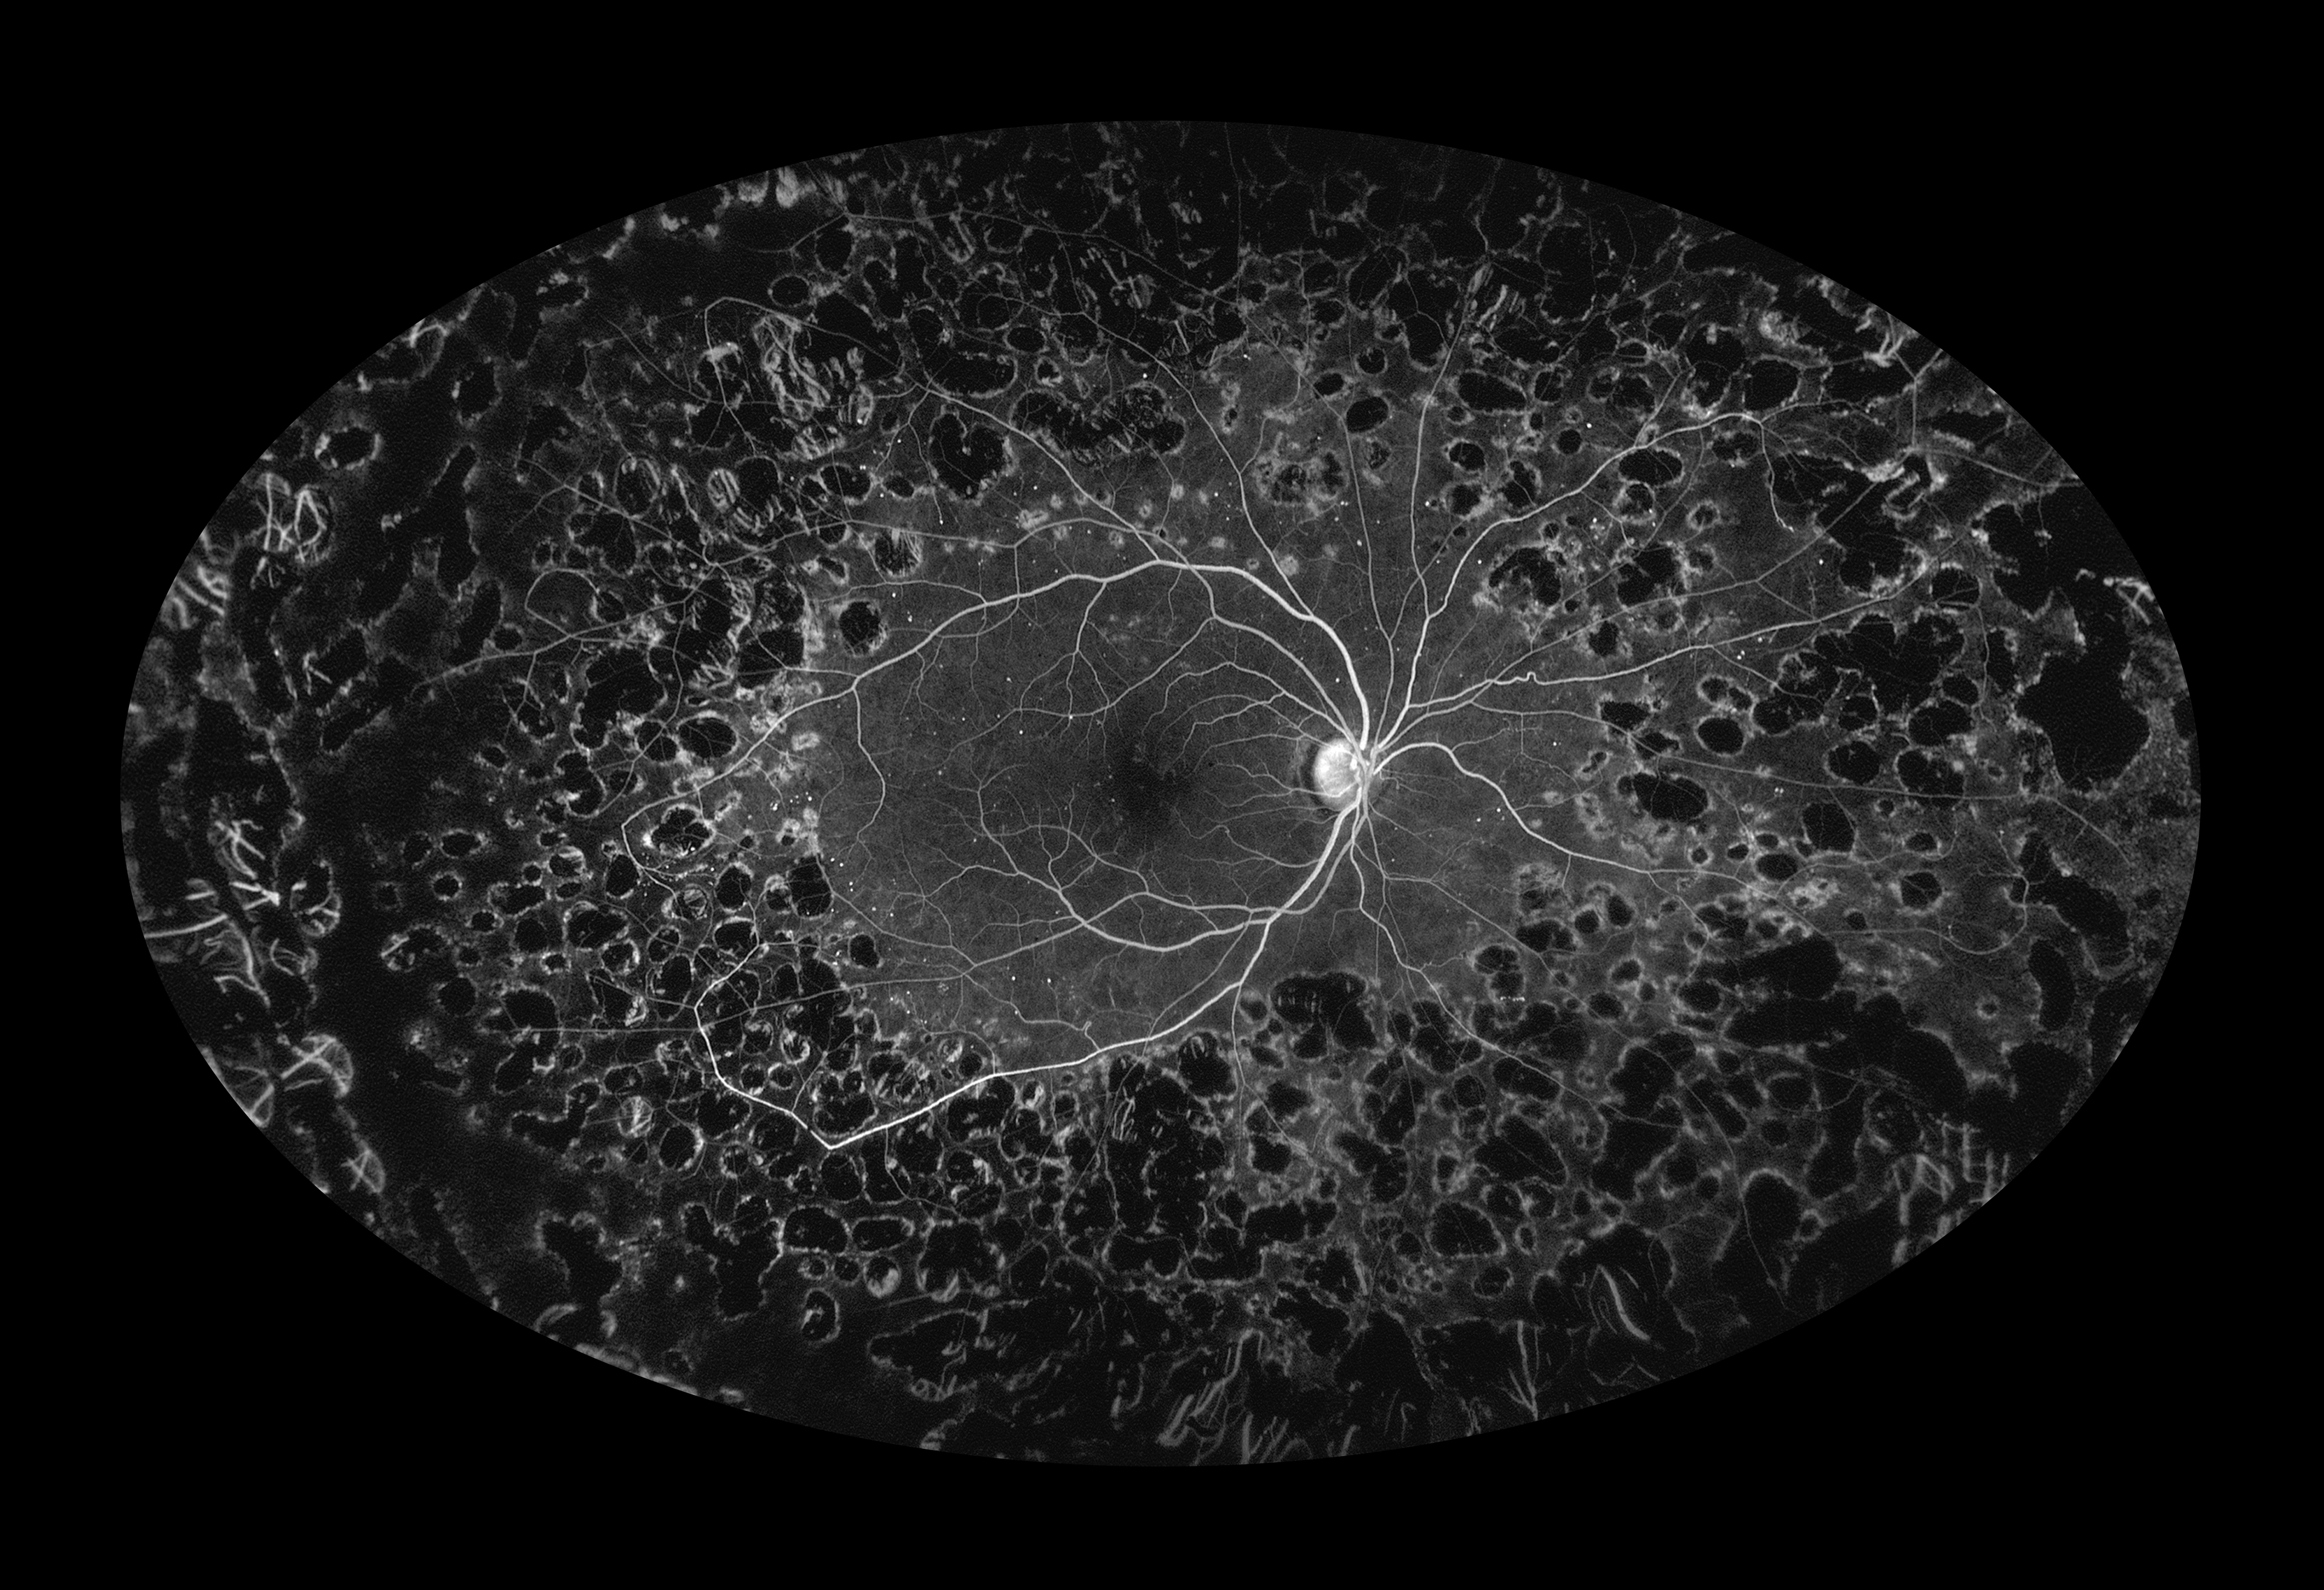

Proliferative Diabetic Retinopathy with Panretinal Photocoagulation Lesions